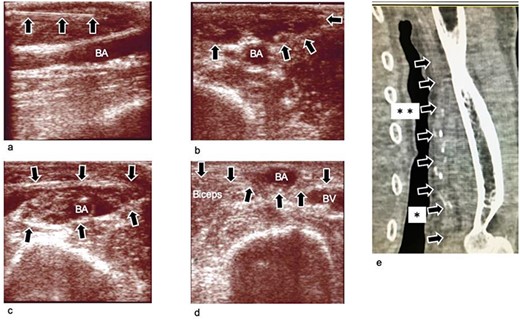

Ultrasound images obtained during and after the operation, (a) Ultrasound image obtained during infusion of TLA solution into subcutaneous tissue. The needle is clearly seen (arrow mark). (b) Ultrasound image obtained after infusion of the TLA solution into the subcutaneous tissue. The subcutaneous tissue becomes edematous (arrow mark). (c) Ultrasound image obtained after infusion of the TLA solution around the BA. The compartment becomes edematous. The BA is dissected from the fascia surrounding it. (d) Ultrasound image obtained 3 weeks after the operation. The BA is transposed to the subcutaneous layer, which is superficial to the brachial fascia (arrow). (e) Plane computed tomography image obtained 4 weeks postoperatively. The BA (arrow marks) is transposed to the subcutaneous layer. The transposed lesion was between arrow marks with * and **. The transposed length was 10 cm, and the depth of the lesion was 2 mm, which was just beneath the skin. BA: brachial artery; BV; brachial vein; TLA: tumescent local analgesia.

We performed a right brachial artery (BA) superficialization for creating a new vascular access as it was necessary to ligate the chronic AVF. First, a total of 42 ml of tumescent local analgesia (TLA) solution (430 ml of normal saline, 20 ml of sodium bicarbonate, 50 ml of 1% lidocaine and epinephrine at a concentration of 1 000 000:1) was injected into the subcutaneous tissue of the right upper arm and around the right BA under the brachial fascia (Fig. 1). A 2-cm skin incision was then created (Figs 2a, b and3a) 3 cm proximal to the cubital crease. The subcutaneous tissue and brachial fascia were subsequently divided along with the course of the BA using a 15-mm wide and 10-cm long retractor and forceps. This procedure created a subcutaneous tunnel to transpose the BA. Then, the BA was exposed (Fig. 2a and b). The BA was dissected from the fascia, the brachial veins and the median nerve using the same retractor and forceps. The branches of the BA were ligated using a vessel ligation clip (LIGACLIP, Ethicon, Inc., Cincinnati, USA) and divided. The brachial fascia was incised to transpose the BA, and the fascia was closed with a running suture using a 4-0 absorbable barbed suture (Stratafix spiral, Ethicon, Inc., Somerville, USA) beneath the BA. A total of 10 cm of the BA was transposed to subcutaneous plane (Fig. 3d, e and f) and superficialized (Fig. 1e). No drain was placed. We then, ligated and divided the AVF on the left forearm.